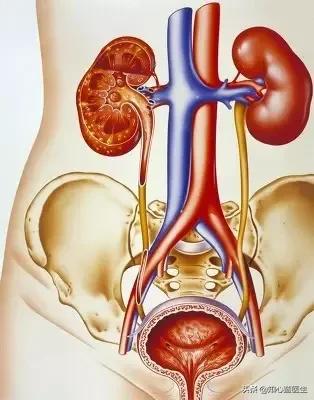

Le rôle principal des reins dans l'organisme est la désintoxication et la détoxication. Le principe est que les reins peuvent produire de l'urine, puis utiliser l'urine comme conduit pour métaboliser les déchets et les poisons produits par le corps. En même temps, ils absorbent d'autres substances utiles à l'organisme. Bien entendu, les reins ont également des fonctions endocriniennes, produisant de l'érythropoïétine, des prostaglandines, des kinines, etc. Grâce à ces fonctions des reins, la stabilité du milieu intérieur peut être assurée.

La relation entre l'hypertension et les reins est à la fois étroite et complexe, et les dommages causés aux reins par l'hypertension comprennent principalement : ① la néphrosclérose : au début de l'évolution des patients atteints d'hypertension essentielle légère et modérée, pendant une période assez longue, il n'y a pas de changements structurels et fonctionnels évidents au niveau des reins, seulement le spasme des petites artères rénales et l'affaiblissement de la fonction d'autorégulation rénale, comme la réduction de la capacité d'adaptation à des états non physiologiques tels qu'une charge élevée en sodium et une expansion volumique aiguë. Après un certain temps, en raison du spasme continu des petites artères rénales, celles-ci subissent une dégénérescence, un durcissement et un rétrécissement, et les unités rénales subissent une atrophie et une sclérose dues à l'ischémie, ce qui nuit gravement à la fonction rénale. L'hypertension primaire se manifeste d'abord par des lésions des tubules rénaux et des changements fonctionnels, le patient se manifeste par une nycturie accrue, les tests de laboratoire révèlent une petite quantité de protéines dans l'urine, principalement des protéines à petites molécules (la β2 microglobuline est un trait caractéristique), la gravité spécifique de l'urine est réduite et la capacité d'acidification de l'urine est diminuée. En général, l'hypertension primaire continue à se développer régulièrement et une petite artériosclérose rénale légère à modérée peut apparaître après 5 à 10 ans. ② athérosclérose de l'artère rénale : l'hypertension est un facteur causal important de l'athérosclérose, et l'artère rénale est un site privilégié de l'athérosclérose. L'artériosclérose rénale réduit le flux sanguin rénal, active le système rénine-angiotensine-aldostérone, provoquant une vasoconstriction, une rétention de sodium et une nouvelle élévation de la pression artérielle, formant ainsi un cercle vicieux. Environ 7 % des patients atteints d'hypertension primaire présentent une augmentation soudaine et progressive de la pression artérielle au cours de la maladie, qui se transforme en hypertension maligne. Lorsque la pression artérielle évolue vers une hypertension aiguë, une nécrose fibrinoïde des petites artères rénales se produit, et les reins sont gravement ischémiés, avec une détérioration rapide de la fonction rénale et une progression rapide vers l'urémie.

- L'hypertension entraîne une insuffisance rénale principalement en endommageant les petites artères des reins. Une hypertension artérielle prolongée entraîne un durcissement des petites artères rénales, qui se manifeste par un épaississement de la paroi interne des vaisseaux sanguins et un rétrécissement de la lumière.

- Lorsque ces petites artères qui alimentent les reins en sang sont rétrécies, l'apport de sang aux reins est naturellement réduit. Une insuffisance prolongée de l'apport sanguin aux reins peut conduire à une néphropathie ischémique, entraînant des problèmes au niveau des glomérules, une atrophie tubulaire et de l'interstitium des reins.

- Les reins sont constitués de glomérules et de tubules. Les glomérules sont comme un tamis qui élimine les déchets dont l'organisme ne veut pas et conserve les protéines dont l'organisme a besoin. L'urine qui passe par le glomérule est appelée urine primaire. Le glomérule est un tamis grossier, et l'urine primaire contient de nombreuses autres substances dont l'organisme a besoin, comme de l'eau et du glucose au maximum, qui doivent être réabsorbées et réutilisées.

- Une fois que les tubules rénaux ont absorbé l'eau et le glucose, l'urine originale est concentrée et devient l'urine finale, qui est excrétée du corps. Le corps humain produit 180 litres d'urine primaire par jour, alors que seulement 1,5 litre d'urine est finalement excrété du corps, ce qui est attribué à la fonction de concentration des tubules rénaux. Si les tubules rénaux sont endommagés, la fonction de concentration est vouée à diminuer, ce qui entraîne une plus grande quantité d'urine.

- L'hypertension entraîne une ischémie rénale, et les tubules rénaux sont plus sensibles à l'ischémie que les glomérules. Par conséquent, le premier symptôme d'une lésion rénale précoce est une mauvaise fonction de concentration tubulaire, qui se manifeste par une augmentation de la nycturie.

Parmi les adultes de plus de 18 ans en Chine, au moins une personne sur quatre souffre d'hypertension artérielle, et l'incidence de l'hypertension artérielle continue d'augmenter. Le rein est un organe étroitement lié au développement de l'hypertension. Nous savons tous que le rein est responsable de la régulation de l'équilibre eau-sel dans l'organisme (équilibre liquide-électrolyte), l'augmentation de l'eau et du sel dans l'organisme entraîne facilement une augmentation de la pression artérielle ; et l'augmentation de la pression artérielle affecte l'hémodynamique des reins, entraînant des lésions rénales. C'est pourquoiLes reins sont à la fois l'organe régulateur de la pression artérielle et l'organe cible des lésions dues à l'hypertension, et il existe un cercle vicieux entre l'hypertension et les lésions rénales.。

L'hypertension à long terme, si elle n'est pas contrôlée, peut conduire à l'athérosclérose des petites artères rénales, à l'hypoplasie rénale, à l'hypoplasie rénale, à une nouvelle augmentation de la pression artérielle, ce qui entraîne un cercle vicieux, et finalement, la fonction rénale continue à se détériorer, devenant une urémie.

L'hypertension artérielle peut également entraîner une atrophie des reins.

Les reins normaux sont ronds et pleins, et l'hypertension artérielle à long terme entraîne un rétrécissement des reins des patients, avec une surface granuleuse et une diminution de la fonction rénale.

1、Comment fonctionnent les reins ?

Lorsque le sang traverse le glomérule, ce dernier équivaut à une membrane de filtration dont les mailles sont très petites, de sorte que les petites molécules telles que l'eau, les électrolytes, le glucose, la créatinine, etc. peuvent être filtrées pour former la proturie, tandis que les cellules sanguines (érythrocytes, leucocytes, plaquettes, etc.), les protéines (albumine, globuline) et d'autres substances relativement grosses ne peuvent pas être filtrées. Bien entendu, cette urine primaire n'est pas l'urine finale que nous excrétons ; les matières premières doivent être réabsorbées et concentrées avant de devenir l'urine que nous excrétons.